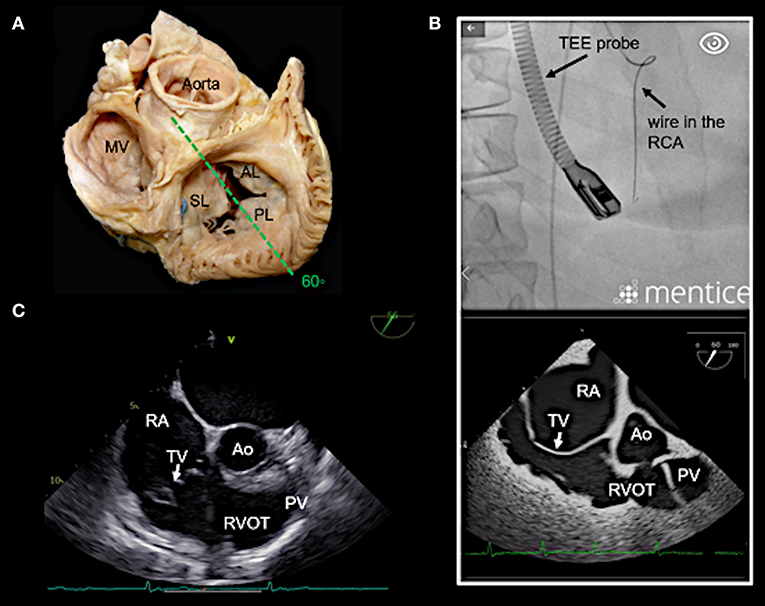

Figure 5. Right ventricular (RV) inflow-outflow tract view (50–70°) as seen in mid- to deep esophageal views. (A) The imaging plane for the RV inflow-outflow tract is found here in a deeper transesophageal view at 60° (see also Figure 3A). (B) The upper picture shows the positioning of the TEE probe in fluoroscopy (35° RAO, 6° CRANIAL). (C) A 2D TEE RV inflow-tract view is shown (slightly higher mid-esophageal position of the TEE probe). Ao, aorta; RVOT, right ventricular outflow tract; PV, pulmonary valve; other abbreviations see Figure 3.